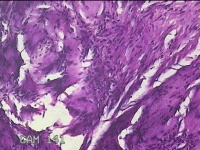

左示指肿物

性别

男

年龄

35岁

临床诊断

左示指末节肿物性质待查?

一般病史

发现左示指肿物

标本名称

大体所见

灰白暗红色肿物0.7x0.3x0.2cm一个,表面糜烂,切面灰白暗红色,质软。